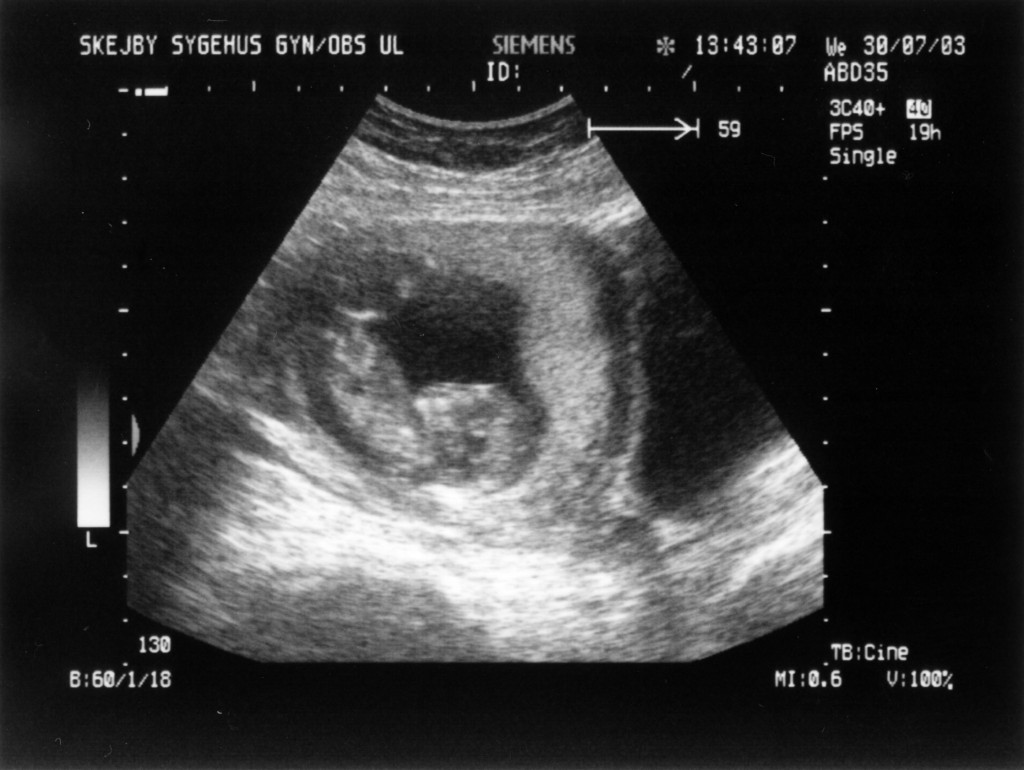

Ultralydsskanning den 30. juli 2003

Vi har i dag været på Skejby Sygehus og få foretaget en ultralydsskanning af baby. Der var kun én (pyh)! Baby blev målt og gennemset for eventuelle misdannelser. Der blev set efter at kraniet var begyndt at blive dannet og at der var to hjernehalvdele. Vi så to arme og to ben og der var fem fingre på den hånd vi så. Vi så også hjertet slå. Til sidst blev der blev målt bredden på nakkenfolden for at vurdere risikoen for mongolisme. Man kan læse mere om ultralydsskanningen her.

Konklussionen var, at alt var som det skulle være, men baby selv var ikke tilfreds. Den lå og sparkede og slog omkring sig og tog sig til hovedet.

Du kan se de billeder vi fik fra skanningen herunder.